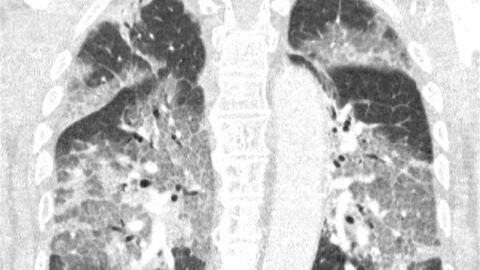

Muestran los pulmones de un paciente en la UCI que rechazó vacunarse contra el coronavirus

El paciente no quiso recibir a vacuna de AstraZeneca por miedo a los efectos adversos y ahora, ingresado en la UCI, sus médicos han mostrado el estado de sus pulmones para concienciar sobre la vacunación y han criticado al ministro de Sanidad por mantenerla paralizada.

El rechazo de algunas personas a recibir una dosis de la vacuna de AstraZenecacontra la COVID-19 por miedo a los efectos secundarios comienza a tener las primeras consecuencias. Médicos holandeses han mostrado el estado de los pulmones de un paciente que se negó a inyectarse la dosis por miedo. Ahora, ingresado en la UCI, los doctores han compartido las imágenes de las radiografías para concienciar a las personas sobre lo que provoca el coronavirus y animar a la vacunación.

Los médicos han publicado una carta abierta dirigida al ministro de Sanidad del país, Hugo de Jonge, como crítica a la paralización del uso de vacunas contra el coronavirus. Relatan el ingreso en la UCI de un paciente no vacunado y cómo es su estado con respiración asistida mientras lucha contra la enfermedad. "Oímos el tremendo pesar en su voz y la desesperación en sus ojos. El virus lo ha atacado y podría haberse evitado. Con su permiso, compartimos su escáner de pulmón. No es necesario ser un especialista en pulmones para reconocer la devastación, ni epidemiólogo para explicar los riesgos de no estar vacunado", relatan en la carta.

Con estas palabras y la imagen pretenden concienciar a la población sobre los beneficios de la vacunación y, por eso, han querido mostrar de manera gráfica lo que recibir una dosis de cualquier vacuna puede evitar. Además han recalcado que "“el riesgo de daño grave causado por el covid-19 es diez veces mayor para las personas de 40 años y 70 veces mayor para las de 60 años, que el riesgo de daño grave por trombosis".